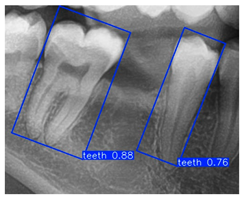

Although YOLOv10n-OBB demonstrated a slight advantage in overall classification accuracy, YOLOv8n-OBB achieved a relatively higher mAP50–95 of 78.75%. Furthermore, as illustrated in Figure 12, YOLOv8n-OBB generated predictions with higher confidence scores, and its detection boxes more comprehensively encompassed critical surrounding structures of the teeth, including both the crown and root regions. In contrast, YOLOv10n-OBB, despite exhibiting better classification accuracy, often produced detection boxes with insufficient coverage or positional deviations, which could compromise the accuracy and stability of subsequent localization and contour segmentation tasks. Considering both model performance and practical image application, the stable and reliable predictions provided by YOLOv8n-OBB better meet the requirements of fine-grained dental feature recognition. Moreover, its robustness is advantageous for downstream applications such as auxiliary line generation and implant pathway orientation.

Figure 12.

YOLO-OBB segmentation comparison.